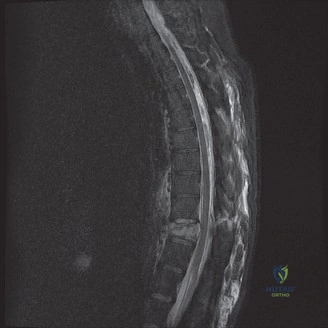

Pre-Operative Planning, Templating, and Patient Positioning

When surgical intervention becomes unavoidable, meticulous pre-operative planning is the cornerstone of a successful outcome. Advanced imaging is non-negotiable. An MRI with and without gadolinium contrast is the gold standard for defining the extent of the epidural abscess, the degree of neural compression, and the involvement of adjacent paraspinal musculature (e.g., psoas abscess). T1-weighted images typically show hypointense signals in the infected marrow, while T2-weighted and STIR sequences reveal hyperintense fluid and edema in the disc space and vertebral bodies. Gadolinium enhancement highlights the vascularized inflammatory phlegmon and the capsule of any abscesses.

In addition to MRI, a fine-cut computed tomography (CT) scan is essential for evaluating bony destruction. CT allows the surgeon to assess bone stock for pedicle screw purchase and to template the size of the interbody cages required for anterior column reconstruction. Upright standing radiographs (if the patient can tolerate them) or full-length supine films are necessary to evaluate global spinal alignment and regional kyphosis.